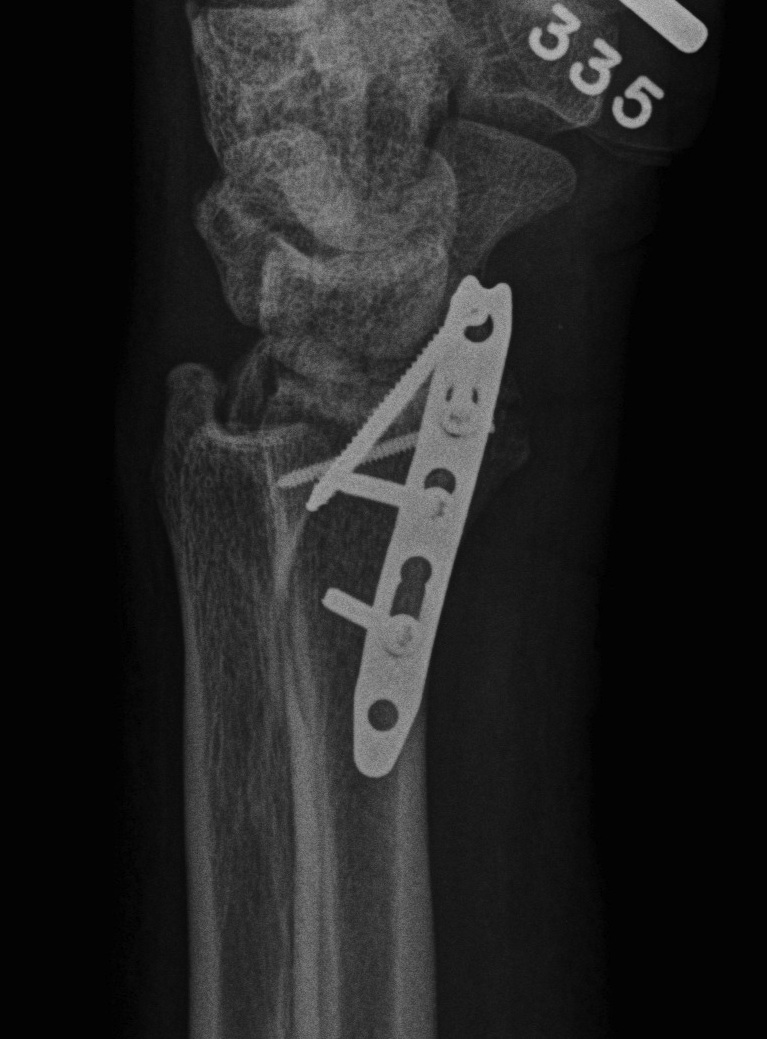

Dorsal Radiocarpal Dislocation ORIF 1Dorsal Radiocarpal Dislocation ORIF 2